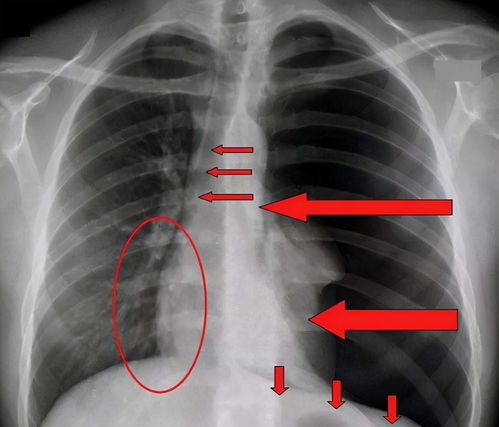

气胸是指气体进入胸膜腔,导致肺部分或全部塌陷的病症,其发病原因主要包括肺部疾病、外力作用以及自发性的原因,对于高瘦男性而言,自发性的气胸较为常见。

1、肺部结构特点:高瘦男性的肺部组织相对较为薄弱,这可能导致肺部在受到外力或内部压力变化时,更容易发生破裂,从而引发气胸。

2、胸腔结构特点:高个子通常具有较长的气管和支气管,这可能使胸腔内的压力分布不均,增加了气胸的发生风险。